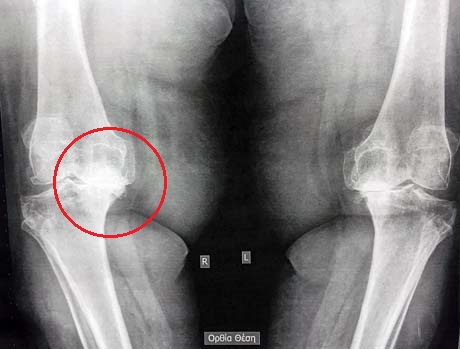

Γυναίκα 89 ετών πάσχει από σοβαρή αρθρίτιδα των γονάτων άμφω. Το δεξί γόνατο προκαλεί ιδιαίτερο πόνο, έχει παραμόρφωση ραιβότητας καθώς και αστάθεια δημιουργώντας προβλήματα στην ασθενή στη βάδιση αλλά και στον ύπνο.

Πριν και 45 ημέρες μετά την χειρουργική επέμβαση. Ο μηχανικός άξονας του κάτω άκρου έχει διορθωθεί πλήρως, η σταθερότητα έχει επανέλθει και ο πόνος έχει εξαφανιστεί.